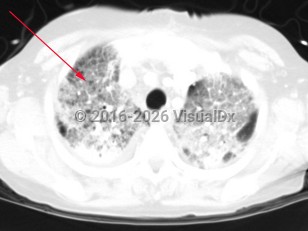

Haemophilus influenzae pneumonia

Symptoms include fever, cough, and shortness of breath. Symptoms may differ depending on the type of pneumonia (either segmental or bronchopneumonia). Patients with a segmental pneumonia can present with abrupt onset of fever and pleuritic chest pain. These patients tend to develop bacteremia more frequently than those with bronchopneumonia. Patients with bronchopneumonia can present with constitutional symptoms, tachypnea, and mild fever. Haemophilus influenzae more commonly presents as a bronchopneumonia.